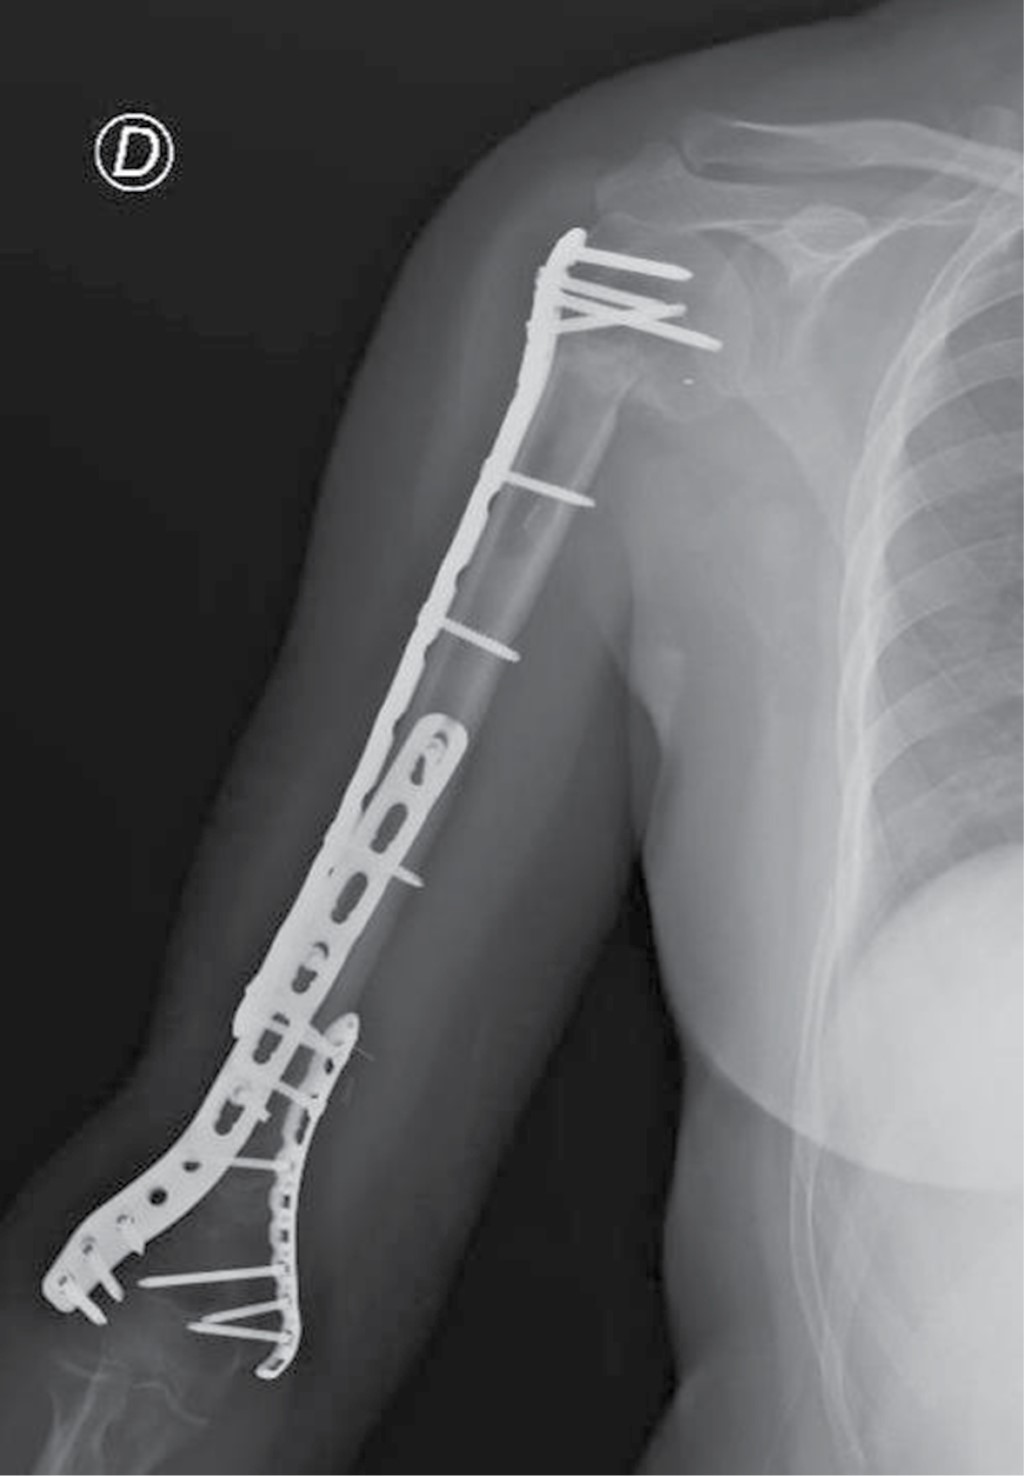

With the required informed consent, this study presents the case of a 36-year-old female patient referred for evaluation by Oncological Orthopedics at the Sebastián de Belalcázar/Colsanitas Clinic, Cali, Colombia, where she had established a clinical history of a mass in the right arm that had increased volume and sensation over the previous six months without a history of trauma or other relevant antecedents. Physical examination revealed a palpable, circumferential, fixed mass between the middle and distal thirds of the right arm, with pain on palpation and preserved ranges of mobility in the shoulder and elbow. Examination by X-ray imaging of the right arm showed a lytic lesion in the humeral shaft with poorly defined edges, cortical thinning, a periosteal reaction and a mass effect with compromise of the soft tissues (Figure 1).

Figure 1